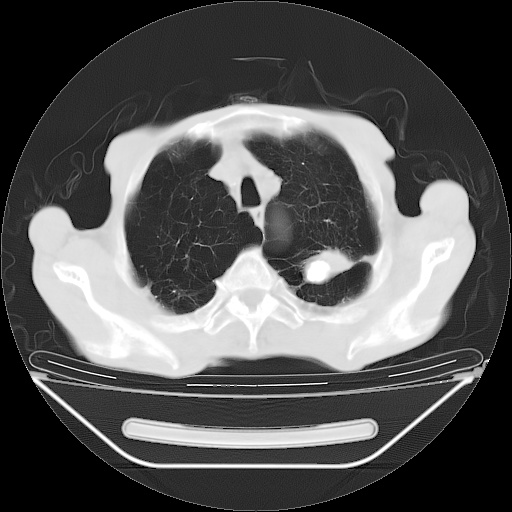

以下是引用zsl6918在2008-8-25 21:55:00的发言:[br]符合右肺周围性肺癌并肺内转移,左肺结核球。双肺肺气肿。腰椎附件转移。

以下是引用随光逐影在2008-8-25 22:03:00的发言:[br]1)考虑右肺下叶周围性肺癌并肺内转移,腰椎附件转移。2)左上肺结核(结核球形成)。3)双肺肺气肿(多发肺大泡形成)。4)双肺门区及纵隔内多发淋巴结钙化。